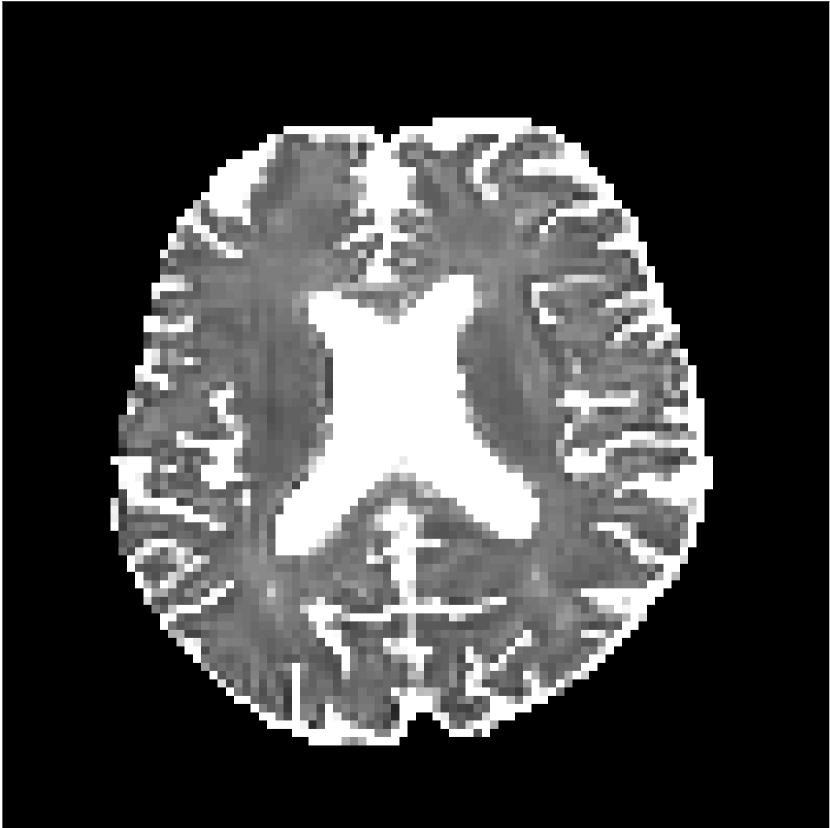

Figure 8 shows examples of non-diffusion-weighted images before and after processing. The raw images (Raw) served as the input for the magnitude deep learning (MCNN) and complex deep learning (CCNN) methods.

Raw

MCNN,

MCNN Resid.,

CCNN,

CCNN Resid.,

No PF

5/8 PF

Both methods remove artifacts, but the MCNN method allows residual rippling artifacts to pass through in the presence of partial Fourier. These rippling artifacts are not present in the CCNN method.